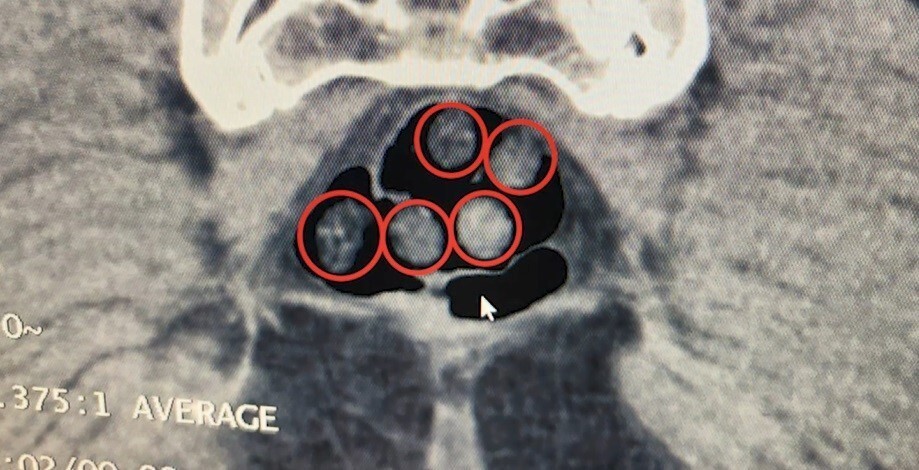

İkinci operasyonda ise Tatvan’da durdurulan bir otobüste yolcu olarak seyahat eden yabancı uyruklu iki şahıs gözaltına alındı. Tatvan Devlet Hastanesi’nde yapılan röntgen ve tomografi incelemelerinde, şahısların mide ve bağırsaklarında çok sayıda yabancı cisim tespit edildi. Yapılan tıbbi müdahale ile şahısların yuttuğu 14 kapsül ve üzerlerinden çıkan 36 kapsül olmak üzere toplam 50 kapsül, 385 gram metamfetamin ele geçirildi.

TATVAN DEVLET HASTANESİNDE YAPILAN RÖNTGEN VE TOMOGRAFİ İNCELEMELERİNDE, ŞAHISLARIN MİDE İLE...